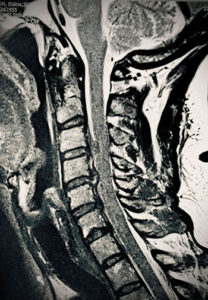

MRI showing cervical disc prolapse with cord compression

Most importantly, we prevent the development of structural changes like disc prolapse, which is a disc bulge or facet joint enlargement, both of which cause spinal pain and stiffness and can narrow the exit holes for nerves and, even worse, your spinal cord.